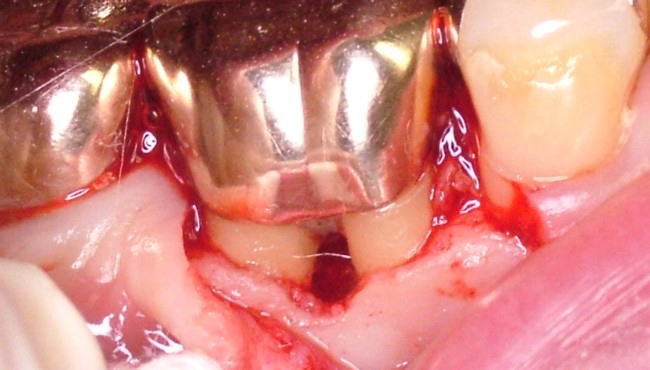

3 根分岐部病変の治療法

根分岐部病変が一旦発症してしまうと、その治療はなかなか困難です。多くの場合大臼歯部で起こるため、その位置的な事情や歯根の懈怠の複雑さなどから、正確な診断、術者側の施術、患者さんの管理などいずれも困難を極めます。

治療法としては様態に応じて、スケーリング・ルートプレーニング・分岐部入り口の整形によって磨きやすい形態を作る→歯槽骨の整形→歯根に対する処置(いずれかの根を抜歯する・複数の根の間を分割するなど)やトンネルの形成などの処置があります。 また「再生療法」として薄い皮膜を用いて歯槽骨の再生を誘導する『組織再生誘導法(GTR法)』や特殊な薬剤を用いる『エムドゲイン法』などがあります。 |